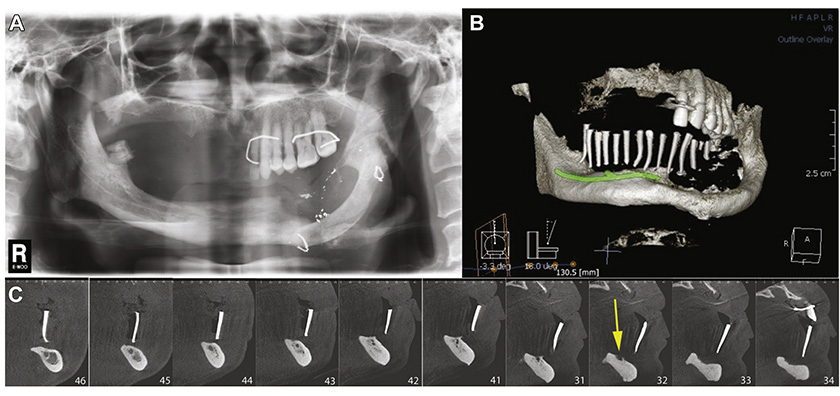

A 59-year-old male patient with a complete edentulous atrophic mandible presented with a chief complaint of a loose-fitting denture that caused pain during function. The left mandible was reconstructed 40 years previously after a gunshot injury by utilizing iliac crest bone. The patient had good medical health and no systemic diseases, such as diabetes or heart disease. He maintained a healthy lifestyle with no history of alcohol or tobacco use. Clinical examinations (orthopantomography and cone-beam computed tomography) showed severe atrophy of the alveolar ridge (class VI, as described by Cawood and Howell (12)) (Fig 1). The crest of the ridge was below the floor of the mouth at the lower level of the genial tubercles with loose connective tissue and no keratinized tissue. Radiographic examination revealed that the inferior alveolar canal was too close to the crest and that the left reconstructed mandibular body deviated out of the mandibular arch. The patient had a bone height of 1-2 mm from the right inferior alveolar canal to the crest of the alveolar ridge, extending from the lower right second molar to the right lower central incisor. The right inferior alveolar nerve passed through the midline and was nearly exposed under the oral mucosa at the anterior part of the mandible (Fig 1). Indeed, the incisive branch of the right inferior alveolar nerve terminated and was exposed at the lower left lateral incisor. The height of the remaining basal bone was also evaluated; particularly, at the position of the lower left canine and the lower left premolar, the height was only 7 mm, which required a bone graft to increase the volume. Moreover, obtuse mandible bone angles are a disadvantage for the placement of implants in a proper direction. As the alveolar ridge was severely resorbed and the inferior alveolar canal was too close to the crest, the guided bone regeneration procedure and conventional implant placement were impossible. Therefore, the surgical plan was right IANT and onlay bone grafting (from the right iliac crest) on the remaining basal bone with immediate placement of 4 implants.

Figure 1. Radiography showed severe atrophy of the alveolar ridge. A, Orthopantomographic view. B, Three-dimensional reconstructed image using multidetector cone-beam computed tomography with illustration of the right inferior alveolar nerve pathway. C, CT slices at positions #46 to #34 showed that the right inferior alveolar nerve was 1-2 mm from the alveolar crest (the arrow shows that the nerve was exposed on the alveolar bone of the left anterior region).